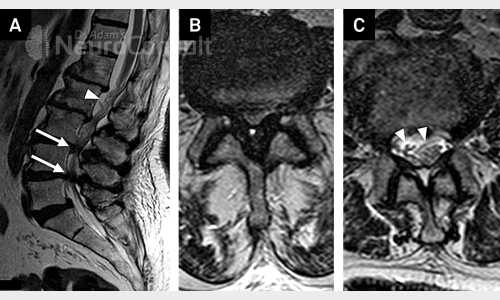

I am an consultant neurosurgeon. I have completed my Masters in General Surgery from SN Medical College, Agra and thereafter completed my formal Neurosurgical training from one of India's premier institute ie. SREE CHITRA TIRUNAL INSTITUTE OF SCIENCES AND TECHNOLOGY, Trivandrum (An institute of national importance). I have special interest in brain and spinal tumors.

I've been involved in numerous treatment of brain and spine-related ailments like spinal joint and disc disease, brain infarction(stroke/paralysis), hydrocephalus etc. to name the few. I am passionate about patient care and strives very hard for their recovery both physically and mentally.